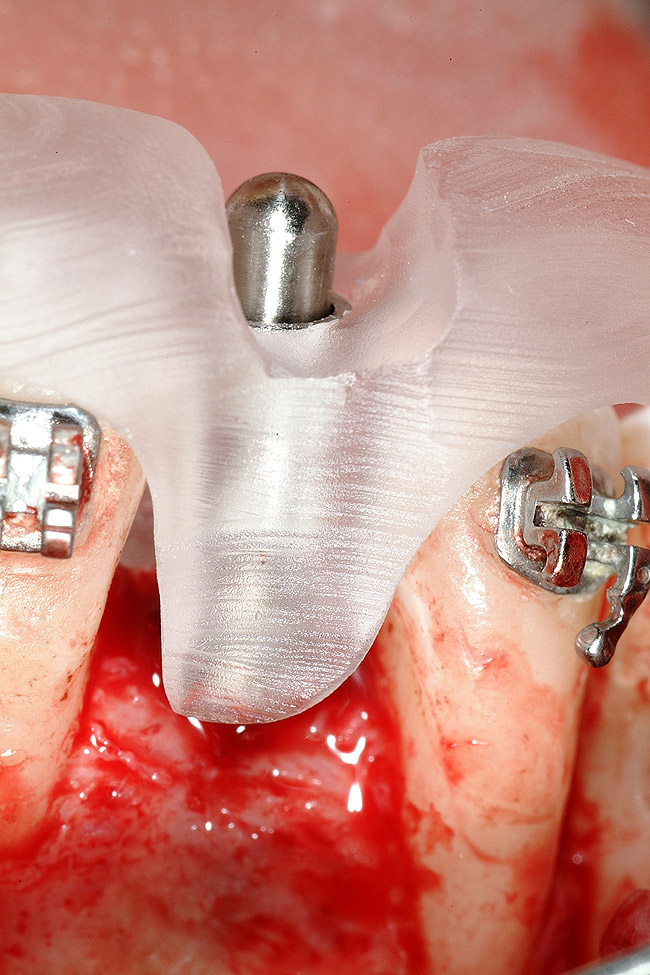

Figure 17  Tooth-supported SurgiGuide (Materialise Dental, Leuven, Belgium) (2 mm level) in place.

Figure 17

Following the first goal of orthodontia—moving tooth No. 22 to a proper functional and anatomical position—a periodontal reevaluation was performed, demonstrating an improvement in short- and long-term tooth prognosis. At this time, the decision was made to abort continual extrusion of teeth Nos. 21 and 22, although some attachment level discrepancy remained between Nos. 21 and 22 (Figure 14). Implant diagnostics ensued and included mounted study models and a diagnostic wax-up. A scanning appliance was created to demonstrate the desired prosthetic outcome requirements, and the patient was referred for computed tomography (CT) scans. CT scan assessment demonstrated successful orthodontically directed GBR to allow implant placement (Figure 15 through Figure 16). Only minor GBR therapy would be needed and could be accomplished simultaneously with implant installation. Guided implant placement occurred, using an open flap approach (Figure 17). During surgery, root dehiscences were noted on teeth Nos. 21, 22, 24, and 25, as well as the anticipated dehiscence following implant placement at No. 23 (Figure 18). A positioning reference (index) was secured after implant placement to facilitate a provisional prosthesis at stage II surgery. Cortical perforations then were placed adjacent to the implant to encourage angiogenesis (Figure 18), and mineralized freeze-dried bone allograft enhanced with platelet-derived growth factor was placed over the dehiscences for purposes of guided tissue regeneration and GBR (Figure 19). A highly resorbable collagen membrane was placed to stabilize the allograft. The flap was coronally repositioned, and primary-intention wound healing was achieved (Figure 20 and Figure 21). Following 4 months of stage I surgery, implant uncovery and immediate provisionalization were performed in conjunction with connective tissue grafting. Final orthodontic tooth movement then ensued, using the implant as anchorage to optimize end-tooth movements, interroot separation, and the cuspid-protected occlusal scheme. A final impression then was secured, and a zirconia abutment (Figure 22) with an all-ceramic restoration was fabricated for the prosthetic phase completion of No. 23 (Figure 23 through Figure 25).